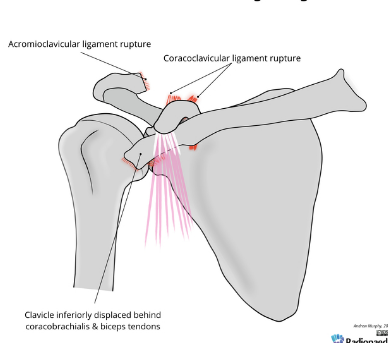

Based off Rockwood classification of acromioclavicular joint injury, what grade would this be?

6